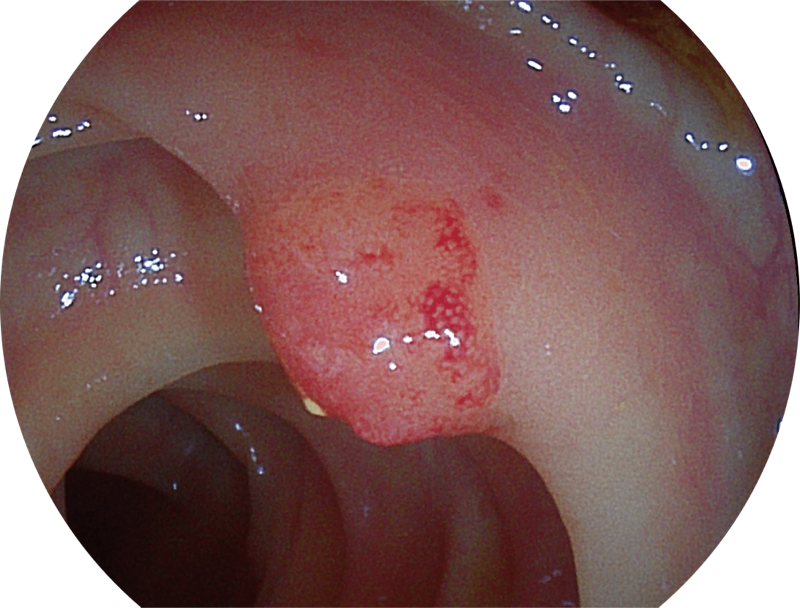

百万级像素高清传感器,1080P全高清视频信号输出,图像清晰。

(Spectral Focused lmaging, SFI)

能够凸显黏膜浅层和中层血管轮廓,适用于中、远景观察下的病灶识别和早癌筛查。